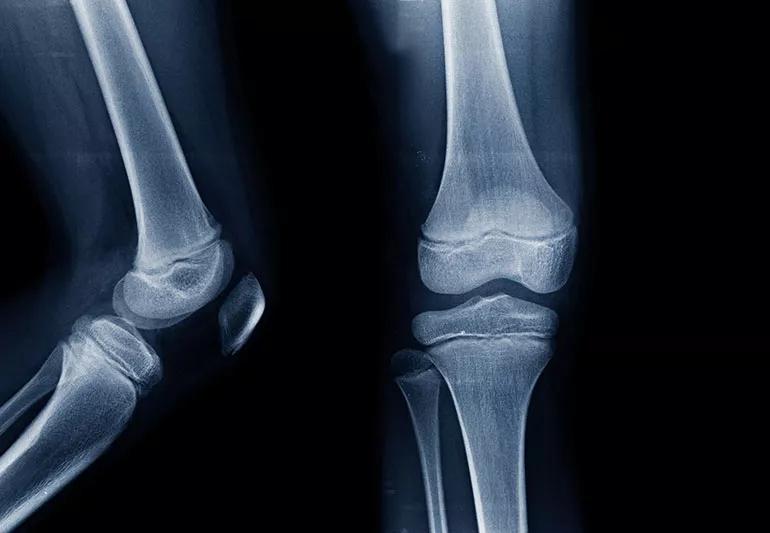

x-ray of joint

Lab studies and X-rays won’t help your doctor diagnose growing pains, although imaging can help rule out other, more serious conditions.